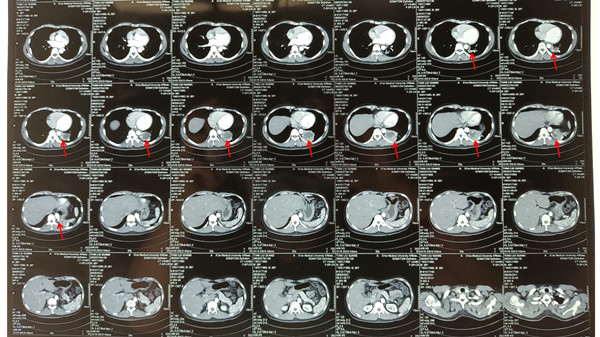

患者田某某,男,38岁,因“发现肺肿物5日余”于2021年09月10日入我院胸外科。入院后行胸部增强CT提示:左肺下叶背段、后基地段实行囊块,多考虑肺隔离症伴感染,合并动脉导管未闭。心脏彩超示:大动脉短轴切面显示肺动脉根部与降主动脉之间可见一管状结构,CDFI:大血管水平可见左向右红色分流彩束,宽约5.7mm,诊断为动脉导管未闭。经胸外科全科讨,并邀请麻醉科吕建瑞教授会诊,最终决定在全麻下行胸腔镜下左肺下叶切除+动脉导管未闭结扎术。

经过充分的术前准备,9月14日上午,在麻醉科进行全身麻醉后,随后胸外科李少民主任团队完整切除了(见图2),并成功结扎动脉导管(见图3),手术过程顺利,历时2小时,术后患者生命体征平稳,顺利拔除气管插管后安全返回胸外科病区,目前患者病情稳定。